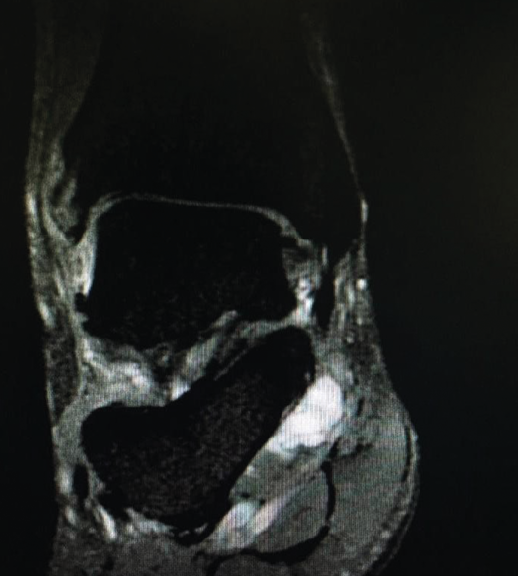

Figura 1. Resonancia magnética, corte coronal en T2. Se observa una lesión ocupante de espacio en el canal tarsiano.

Además, se evidenció el signo de Tinel positivo en el canal retromaleolar del tobillo derecho. La prueba de dorsiflexión-eversión fue positiva, reproduciendo la clínica. No se evidenció atrofia de la musculatura intrínseca plantar. El estudio radiológico simple descartó deformidades o lesiones óseas. La resonancia magnética (RM) objetiva la presencia de una imagen de contenido líquido en el canal tarsiano, compatible con un quiste sinovial o ganglión (Figura 1). El estudio neurofisiológico, mediante electroneurografía y electromiografía, mostró disminución de la velocidad de conducción sensitiva, con afectación de las ramas plantar medial y lateral del nervio tibial posterior derecho (Figura 2 y Tabla 1).